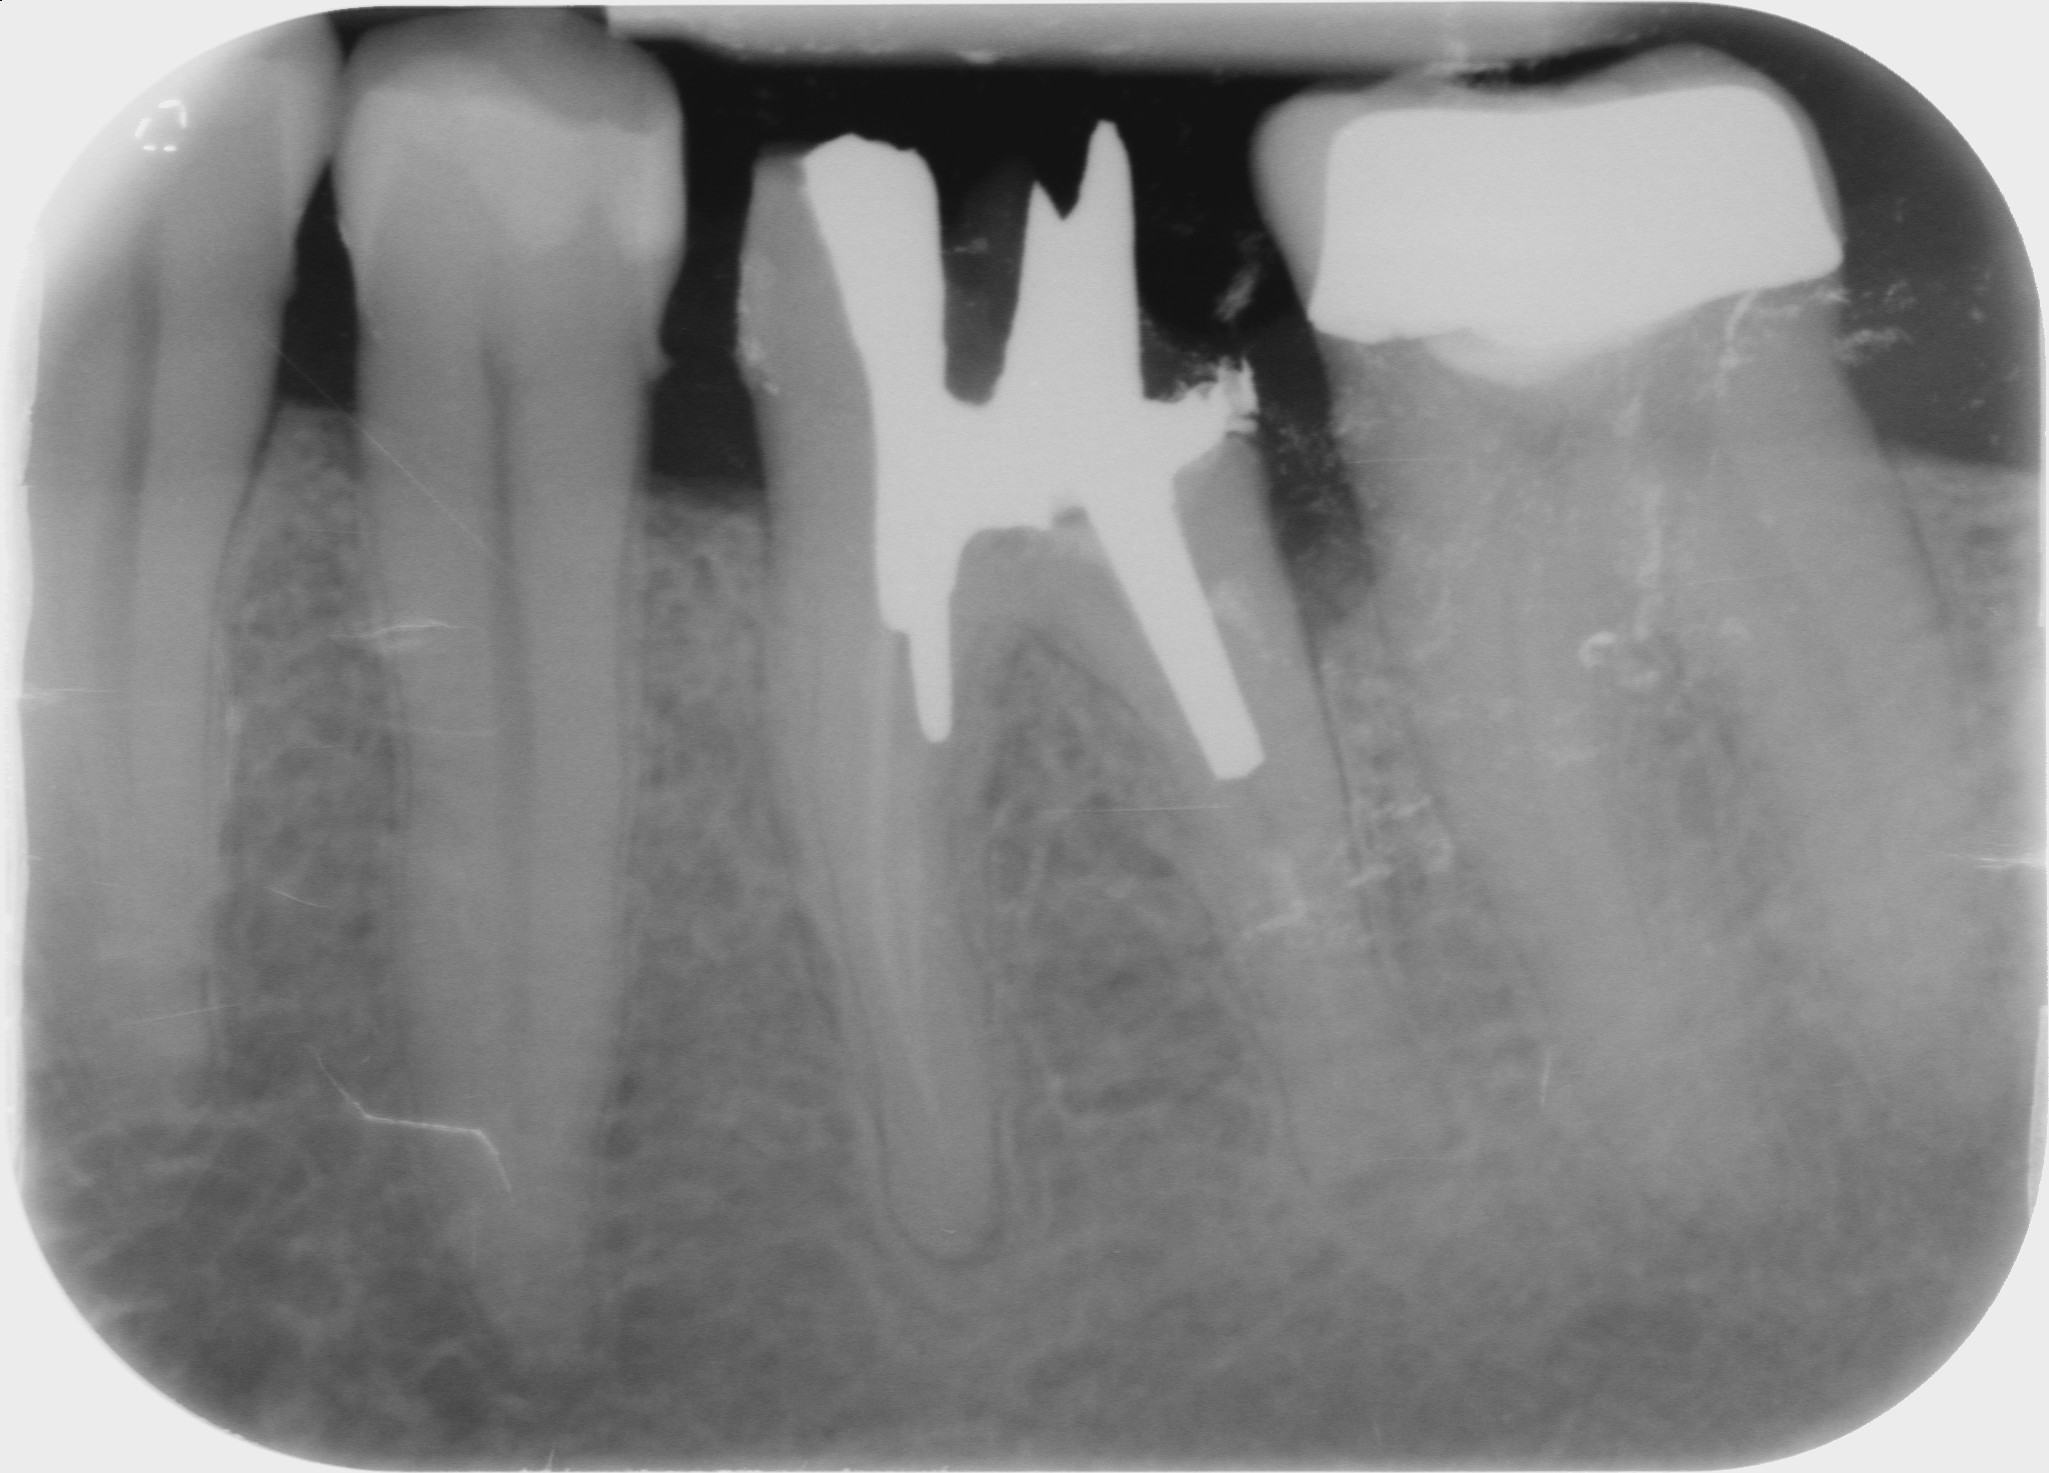

Fig. 2 : Contrôle radiographique en vue d’évaluer l’axe de délogement de la reconstitution corono-radiculaire, ce qui a permis de corriger l’angle de coupe.

D’un point de vue pratique, la première étape consiste à réduire les dimensions du tenon s’il occupe une grande partie de la structure coronaire, de préférence en lui donnant une forme cylindrique similaire à celle d’un tenon préfabriqué. De même, une reconstitution corono-radiculaire coulée ancrée dans plusieurs canaux doit d’abord être sectionnée jusqu’au niveau du plancher de la cavité pulpaire, afin de la traiter comme un ensemble de tenons unitaires, ce qui diminue le degré de rétention global du système. La réduction du tenon doit être effectuée avec des fraises en carbure spécialement conçues pour découper le métal, sous une irrigation abondante. Les évaluations cliniques et radiographies préliminaires sont essentielles pour planifier l’angle de coupe. La procédure doit être fréquemment vérifiée et, si nécessaire, il convient d’effectuer des contrôles radiographiques avant qu’une quantité excessive de dentine ne soit sacrifiée (Figs. 1–3).